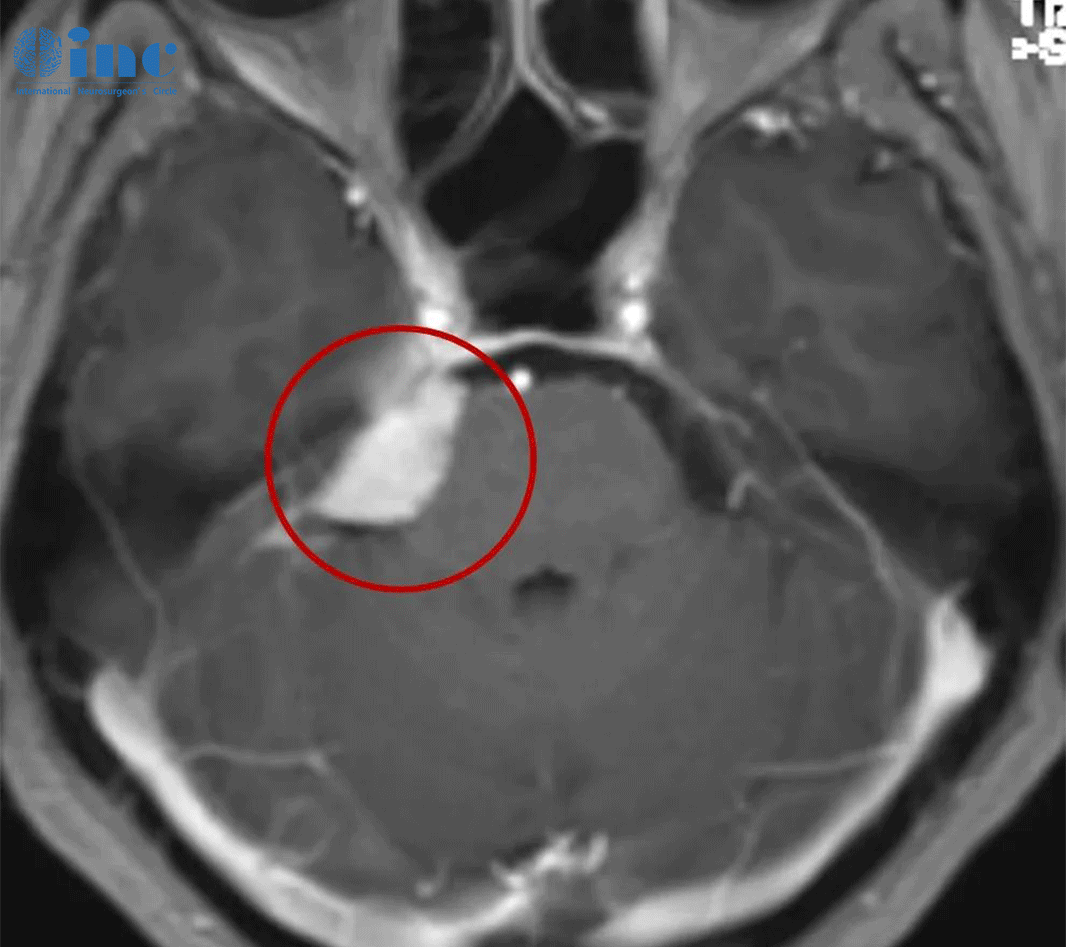

较大脑膜瘤长在大静脉窦、大脑镰旁,INC巴教授手术全切,没有复发、无后遗症

2012年王女士体检时查出左侧额部大脑镰旁脑膜瘤,考虑肿瘤为良性,

自身年纪也比较大,就听取了医生的保守治疗建议。

但随着肿瘤生长,头痛愈发严重,吃止痛药、试用民间秘方都毫无效果。

经多方求医和查询后,王女士找到INC国际神经外科专家巴特朗菲教授,并进行远程咨询咨询。

教授对病情进行分析后给出的治疗建议是:要想达到术后不复发、无并发症、长期生存等效果,

前提是要对肿瘤进行较大水平的全切。

被肿瘤浸润的硬脑膜可以完全切除并用患者自体组织代替,可保留中央前回,复发可能性低于5%。

王女士得到咨询意见后,毅然赴德国接受巴教授的手术治疗。术中肿瘤得以全切、矢状窦成功重建、运动功能区无损伤,预后无并发症、没有复发。如今王女士已恢复如常,如愿开启新的生活计划。